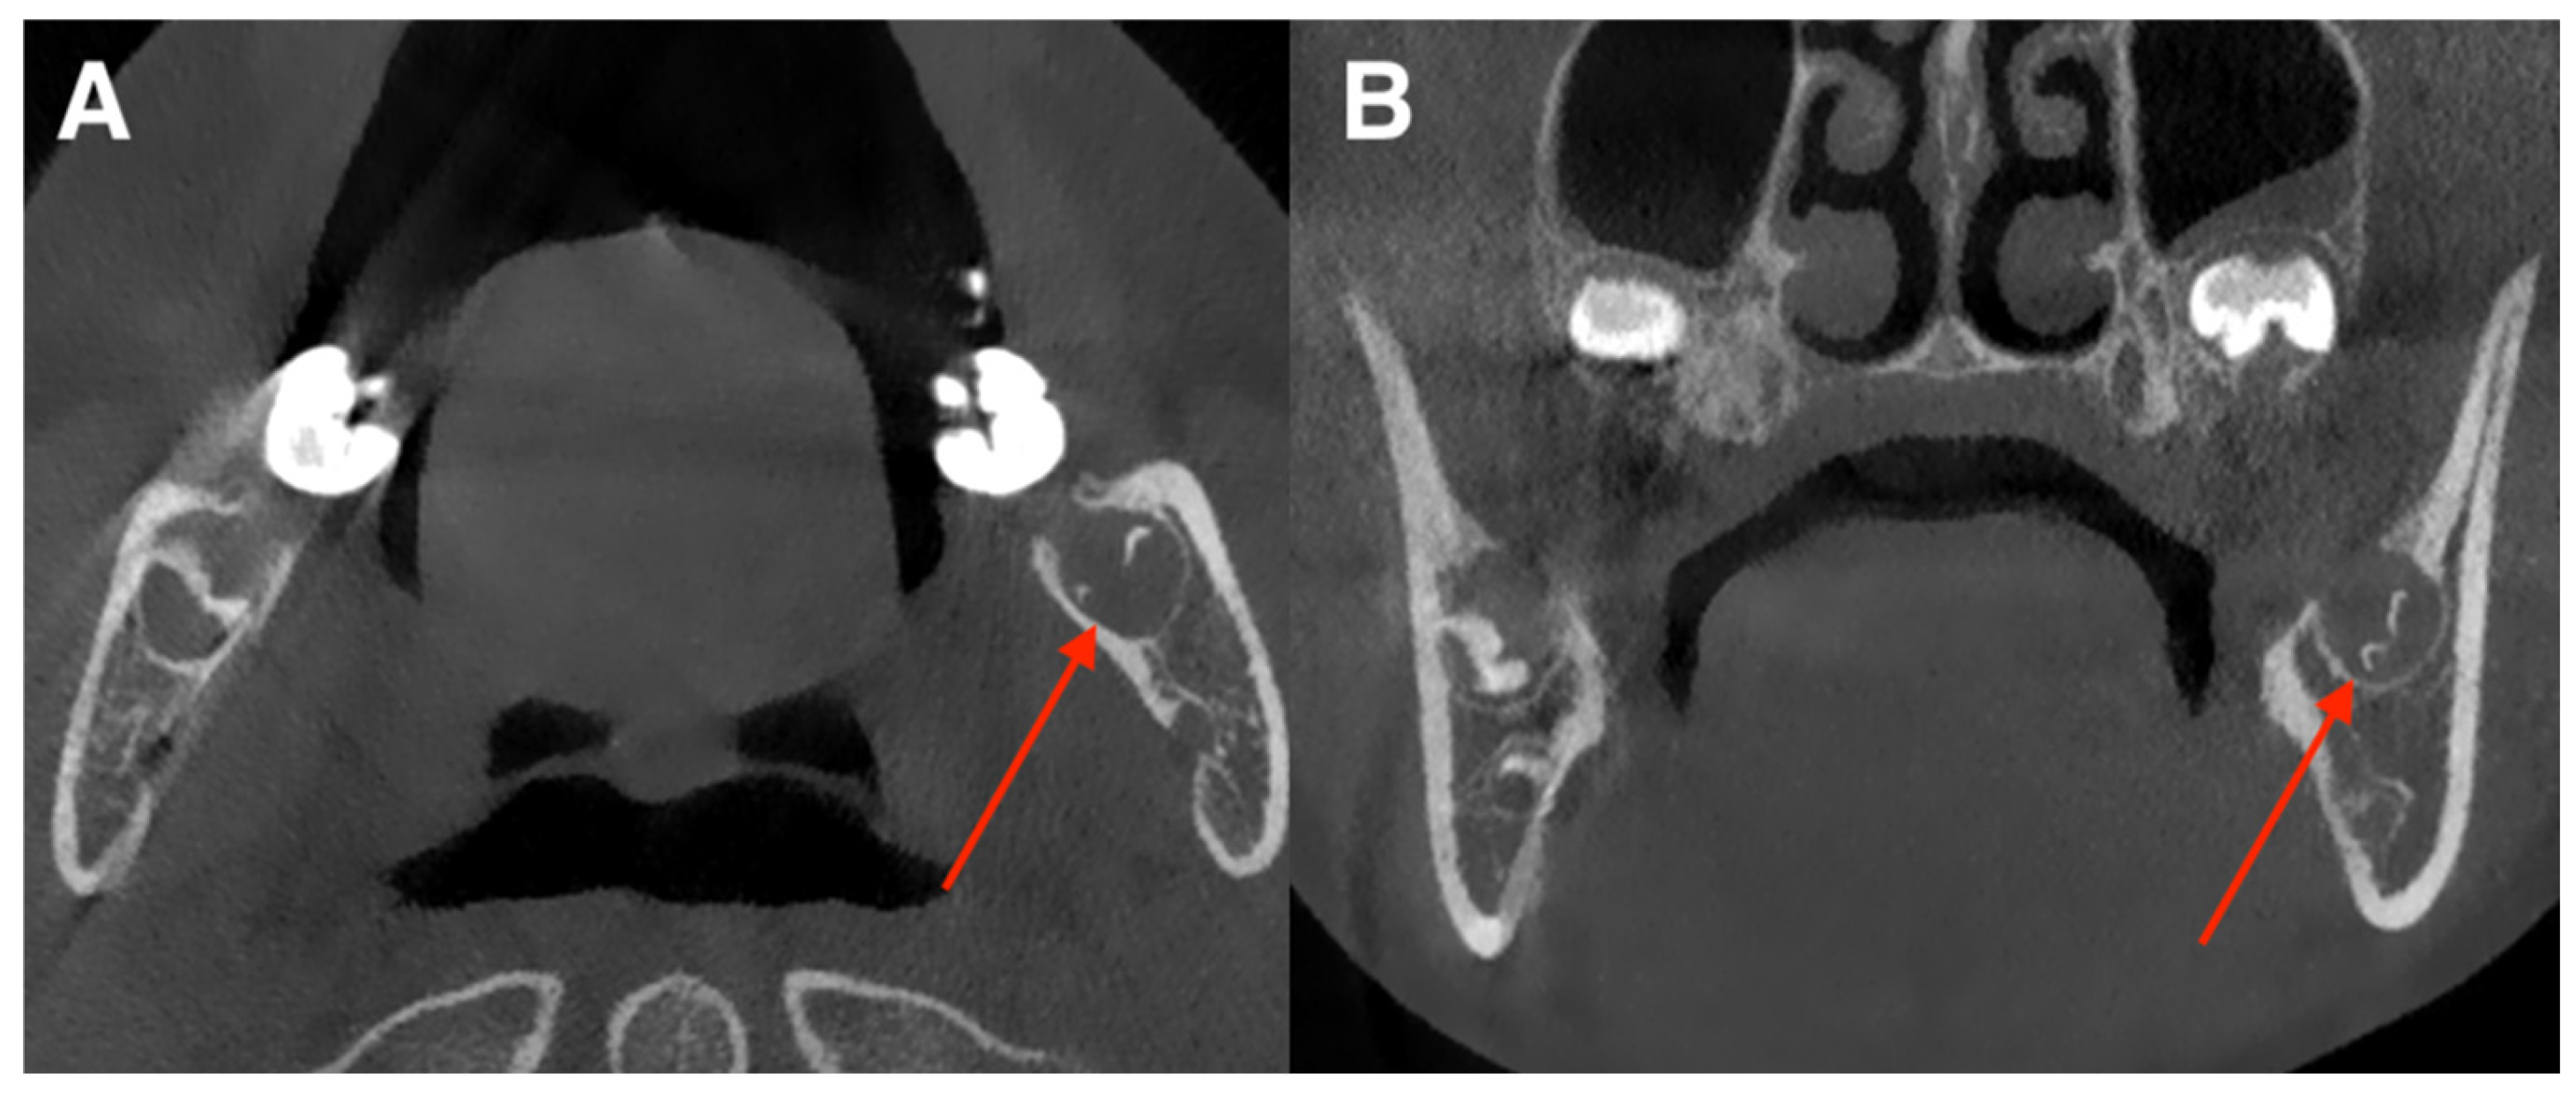

3.3. Anatomical Distribution of Errors

- Tooth 36: 6 errors (4.1% of patients);

- Tooth 27: 3 errors;

- Tooth 21, 11, 17, 14, 46, 38: isolated errors (1–2 cases).